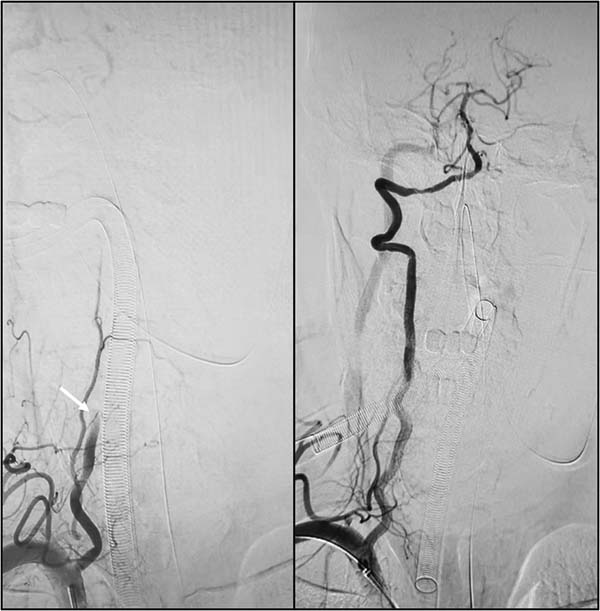

(左图白色箭头所示为闭塞的右椎动脉,右图为术后通畅的右椎动脉)

此次手术难度高、风险大,闭塞血管为维系脑干生命中枢供血的关键通路,且患者血管基础条件差、发病时间久、神经缺损程度严重,术中变数多、操作要求极高。在神经内科负责人孙钦建教授指导下,副主任医师闫鹏带领介入团队,结合术前影像精准研判血管闭塞病因、病变范围及血栓负荷,精准制定手术策略。术中精准操作、精细处置,历时1小时复杂操作,顺利打通闭塞右侧椎动脉,成功实现椎基底动脉系统血流完全再通。术后,患者被转入脑血管重症监护病区,接受后续密切监测与治疗。